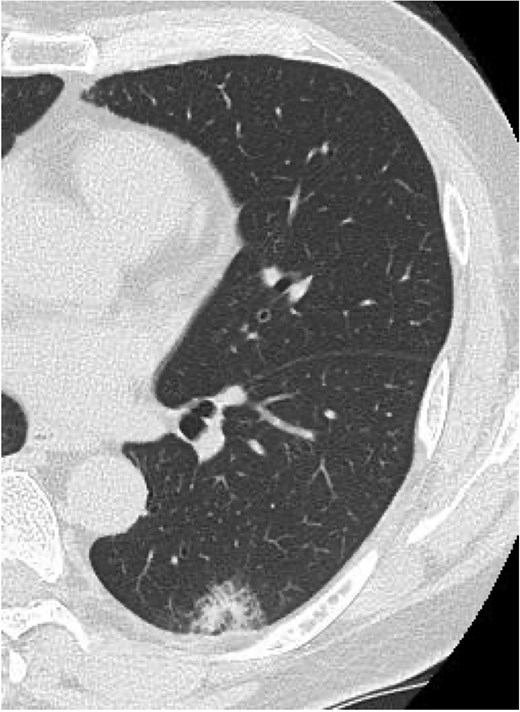

On POD 27, he was readmitted with fever (38.2°C) and respiratory failure. COVID-19 testing was negative. Chest computed tomography revealed patchy consolidations mixed with ground-glass opacities in the right upper lobe with notable expansion, and new ground-glass opacities in the right middle lobe and residual left upper lobe periphery (Fig. 2c). Findings excluded recurrent air leak or aspiration pneumonia. Despite antibiotic therapy, oxygen requirements increased to 2 L by POD 29.

Methylprednisolone pulse therapy (1 g/day for 3 days) was initially administered, followed by oral prednisolone (30 mg). However, oxygen requirements increased to 4 L on POD 31 (Fig. 3). On POD 36, a second methylprednisolone pulse course was initiated with cyclosporine A (150 mg) owing to progressive consolidation on chest imaging (Fig. 2d). Oxygen support was discontinued by POD 38, and he was discharged on POD 52. Follow-up image on POD 104 showed substantial radiological improvement (Fig. 4). Immunosuppressive medications were successfully tapered and discontinued by POD 329. This case was diagnosed as delayed-onset OP as a manifestation of post-acute COVID-19 syndrome, characterized by the biphasic clinical course and distinctive radiological progression occurring weeks after acute COVID-19 infection.

Serial chest imaging demonstrating pulmonary complications. (a) Postoperative day (POD) 10: Initial presentation without significant abnormalities. (b) POD 16: Peripheral ground-glass opacities (arrowheads). (c) POD 27: Patchy consolidation (solid arrows) with new ground-glass opacities and pleural effusion (open arrows). (d) POD 36: Progressive consolidation (solid arrows).